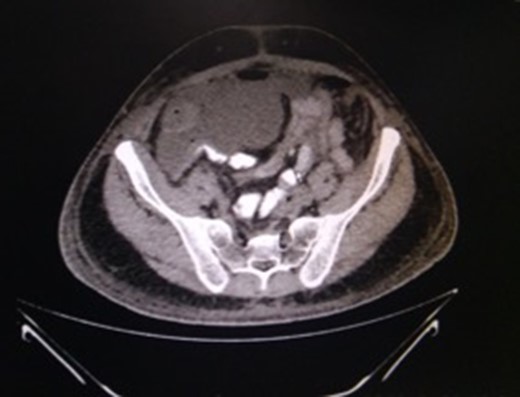

This 50-year-old male had, 4 months previously, undergone an anterior resection of a recto-sigmoid adenocarcinoma, non-anatomical resection of a liver metastasis and diverting loop ileostomy. The pathological report was a moderately differentiated adenocarcinoma and he subsequently received seven cycles of adjuvant chemotherapy. Two weeks after the last chemotherapy cycle he had a contrast study through the distal limb of his ileostomy which was normal. He then underwent a side-to-side hand sewn ileo-ileal anastomotic closure and started passing flatus and stools from the third postoperative day (POD). On POD 4 however he developed lower abdominal distension and a plain X-ray of the abdomen revealed air to be present in the colon and rectum with a few prominent small bowel loops. He then developed massive painless penoscrotal swelling, On local examination the genitals were not tender and there was no elevation of the local temperature (penoscrotal oedema image, Fig. 1). Blood investigations revealed a haemoglobin level of 12.8 g/dl, total leucocyte count of 5900/mm3, serum creatinine of 0.85 mg/dl, total protein 5.18 g/dl and albumin 2.95 g/dl. A urologist’s opinion was sought who opined that the patient might be having common iliac vein thrombosis but a Doppler study of the lower limb and pelvic veins was normal. However the abdominal distension persisted although he was passing flatus and stools. CECT of the abdomen was done on POD-6 and this revealed a large irregular air containing collection extending from the right subhepatic region along the paracolic gutter into the pelvis as well as a fluid collection in the lesser sac extending along the greater curvature of the stomach (CT images). Three percutaneous drains were then inserted—one each in the subhepatic region, pelvis and the left lesser sac and 1500 ml of faeculent content was removed. The patient was kept nil by mouth, started on parenteral nutrition and his antibiotics were upgraded. Over the next 3 days the effluent decreased and the fluid became serous. The penoscrotal oedema also subsided after 4 days (Figs 2–5). On POD-12, a CT scan of the abdomen with oral contrast was done again (CT images), which showed a decreased size of the collection and no well-defined area of extravasation or leak of contrast outside the bowel lumen. The drains were then removed, he was started on oral liquids and later put on a soft diet and discharged on POD-20.

CT-image of drain in situ draining intra-peritoneal leak contents. Source: Department of Radiology, Sir Ganga Ram Hospital, New Delhi.